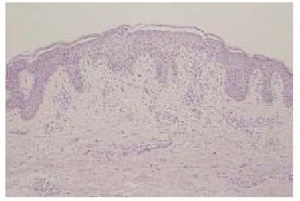

Un varón de 35 años de edad, con antecedentes de seminoma testicular con orquiectomía derecha en mayo de 1997, desarrolló en marzo de 1998 metástasis pulmonares que respondieron a tratamiento con 3 ciclos de BEP (bleomicina, etopósido y cisplatino). Dos años después fue diagnosticado de una leucemia mieloide M4 bifenotípica (linfo/monocitaria), con cariotipo de mal pronóstico [46XY 11q-, t(7,14)], secundaria muy probablemente a etopósido. Recibió tratamiento de inducción con citarabina e idarubicina, sin obtener respuesta. Posteriormente alcanzó la remisión completa con FLAG-Ida (fludarabina, adriamicina, dexametasona e idarubicina). En septiembre del 2000 se le realizó un trasplante alogénico de médula ósea procedente de un hermano con antígeno de histocompatibilidad (HLA) idéntico, previo acondicionamiento con fludarabina y melfalán. El donante presentaba dermatitis atópica, sin otros antecedentes de interés. La profilaxis inicial de EICH se realizó con ciclosporina y metotrexato. El paciente no presentó datos de EICH aguda y fue dado de alta con ciclosporina A, en dosis de 500 mg/día como único inmunodepresor. Se realizó un estudio de médula ósea, que fue normal, y dado que el paciente presentaba buen estado general, sin signos clínicos ni analíticos de EICH, al mes del trasplante se fue reduciendo de forma progresiva la dosis de ciclosporina. A los 50 días del trasplante mientras recibía una dosis de ciclosporina A de 200 mg/día, presentó un exantema maculopapuloso pruriginoso en la zona del escote, espalda y superficie de extensión de extremidades. Se realizó una biopsia cutánea del antebrazo, que mostró marcada espongiosis, exocitosis y formación de vesículas espongióticas (fig. 1). En la dermis papilar existía un marcado infiltrado inflamatorio perivascular superficial con presencia de macrófagos aislados. Se estableció el diagnóstico anatomopatológico de dermatitis espongiótica. No se observaron dermatitis de interfase ni queratinocitos necróticos. Ante este resultado histológico, y considerando que el donante era atópico se realizó determinación sérica IgE, que fue normal. Puesto que el paciente persistía con buen estado general, afebril, sin disnea, diarrea, dolor abdominal, ni otra sintomatología, y el estudio analítico, incluyendo el perfil hepático, no presentaba alteraciones significativas, se continuaron disminuyendo las dosis de ciclosporina A. Así, a los 65 días postrasplante, mientras tomaba una dosis de 100 mg/día, empeoraron las lesiones cutáneas, que afectaban ya a más del 80 % de la superficie corporal. En la exploración física presentaba (figs. 2 y 3) un gran número de pápulas de aspecto liquenoide, de distribución extensa por espalda, extremidades inferiores, cara anterior del tronco y, sobre todo, en miembros superiores, con afectación intensa del dorso de las manos. También se encontraron lesiones liquenoides en mucosa oral, en forma de reticulado blanquecino en ambas mucosas yugales. El paciente persistía con buen estado general, afebril, sin disnea, diarrea, ni otra sintomatología. El perfil hepático en este momento mostraba transaminasas glutamicooxalacética (GOT) de 676 U/l; glutamicopirúvica (GPT), 1.075 U/l, y gammaglutamiltranspeptidasa (GGT), 830 U/l; fosfatasa alcalina, 947 U/l, y bilirrubina, 2,5 mg/100 ml. Se realizó una nueva biopsia cutánea del dorso de la mano, que mostró una dermatitis de interfase con necrosis queratinocítica y degeneración vacuolar basal epidérmica y folicular, compatible con EICH (fig. 4). Con estos datos, el paciente fue diagnosticado de EICH aguda cutánea de grado 3 y hepática de grado 1. Se instauró tratamiento con prednisona, en dosis de 2 mg/kg/día, ácido ursodesoxicólico y ganciclovir profiláctico y se aumentaron las dosis de ciclosporina A a 500 mg/día. El paciente presentó una mejoría progresiva del cuadro cutáneo y hepático, con lo que se inició nuevo descenso progresivo de la inmunosupresión, con buena respuesta, sin aparición de nuevos signos de EICH hasta la actualidad.

Fig. 4.--Detalle de imagen histológica: dermatitis de interfase con marcada degeneración vacuolar y borramiento de la basal epidérmica. Nótese la presencia de aislados queratinocíticos necróticos intraepidérmicos (hematoxilina-eosina).